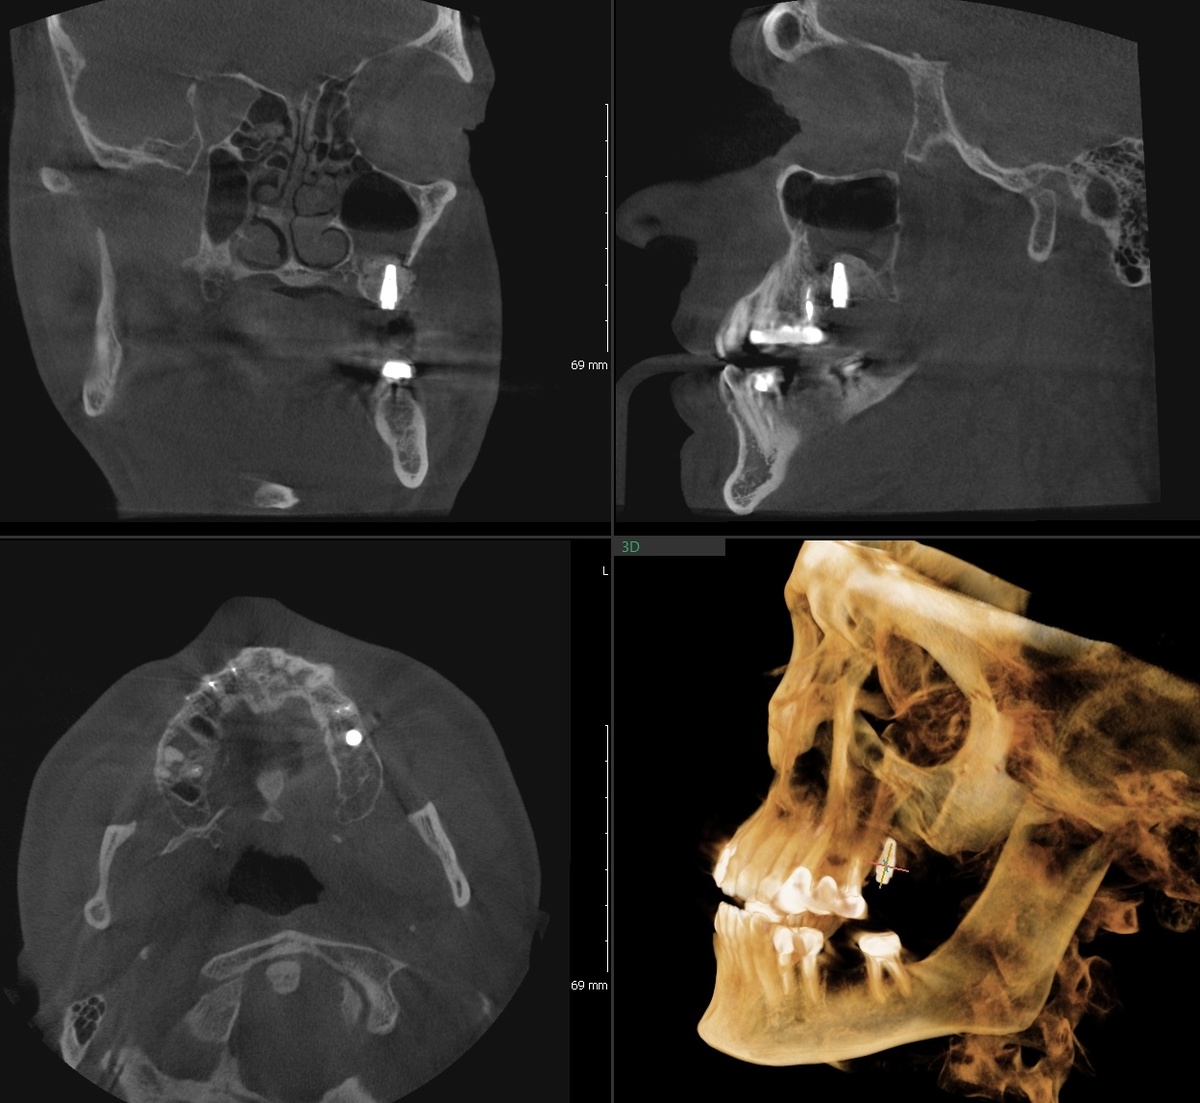

Март 2025 - имплантация зуба-антагониста на нижней челюсти с пластикой десны

Верхняя шестёрка будет, а жевать-то не получится адекватно. Нужен антагонист, зуб на челюсти нижней.

В марте установили имплант на позицию 3.6, нижняя шестёрка слева. С пластикой десны, чтобы вокруг импланта была нормальная прикреплённая слизистая. Покажу КТ в день имплантации выполненное:

Имплантат в области 3.6

Установка проводилась по цифровому протоколу с хирургическим шаблоном. Даже один имплант у нас ставится по навигации - это точность позиционирования и предсказуемый результат.